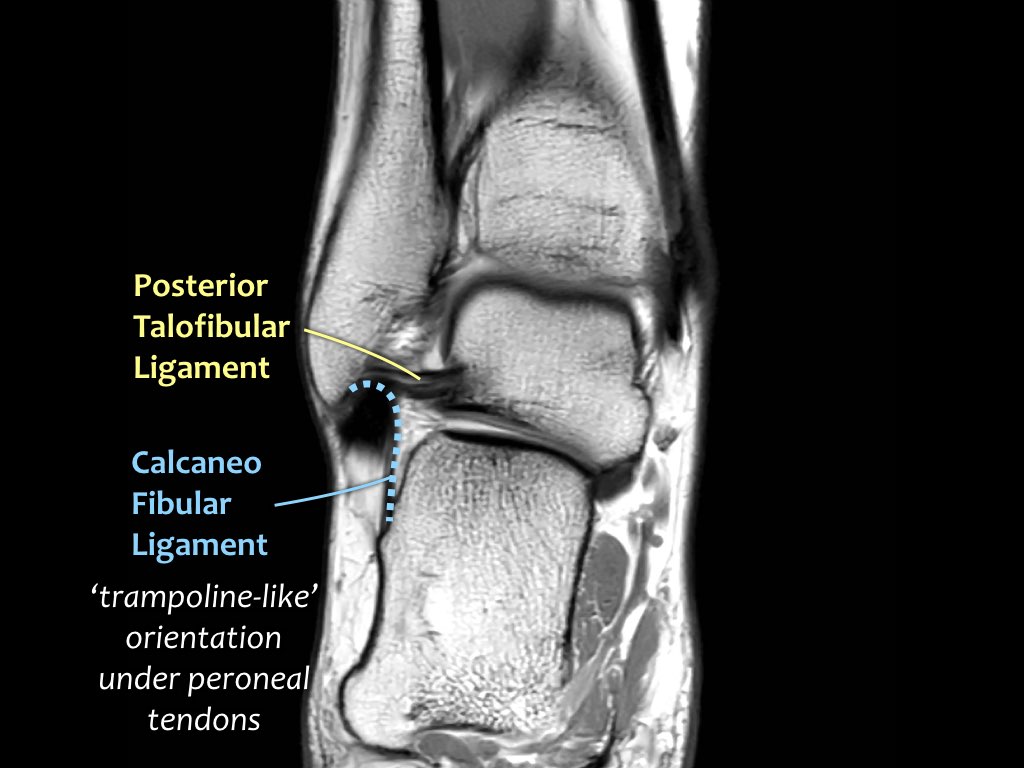

Có ba dây chằng ở phía ngoài:

- Dây chằng sên mác trước (anterior talofibular ligament – ATFL)

- Dây chằng gót mác (calcaneofibular ligament – CFL)

- Dây chằng sên mác sau (posterior talofibular ligament – PTFL).

Dây chằng ATFL chạy từ mắt cá ngoài ra phía trước đến bờ ngoài của xương sên.

Dây chằng này có hướng nằm ngang và được quan sát rõ nhất trên ảnh cắt ngang.

Đây là dây chằng bị tổn thương thường gặp nhất ở cổ chân và cũng là dây chằng đầu tiên bị tổn thương ở phía ngoài.

Điều này có nghĩa là khi dây chằng CFL hoặc PTFL bị tổn thương, rất có khả năng dây chằng ATFL cũng đã bị tổn thương.